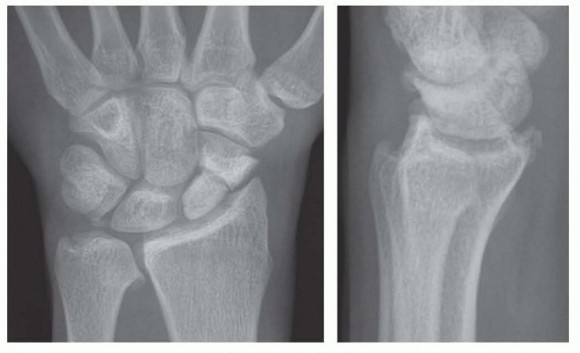

Following the initial resection, the bony fragment is excised, and the osteotomy site is meticulously smoothed using a rongeur or a high-speed burr to eliminate any sharp cortical edges that could abrade the joint capsule or adjacent tendons. Copious irrigation is employed to remove all bone debris, which could otherwise serve as a nidus for heterotopic ossification or third-body wear. Fluoroscopic evaluation in both AP and lateral planes is mandatory at this juncture to confirm adequate resection and verify that the 3-4mm safe zone has not been violated. The wrist is taken through a full, dynamic range of motion under live fluoroscopy to ensure that impingement has been completely eradicated.

Image